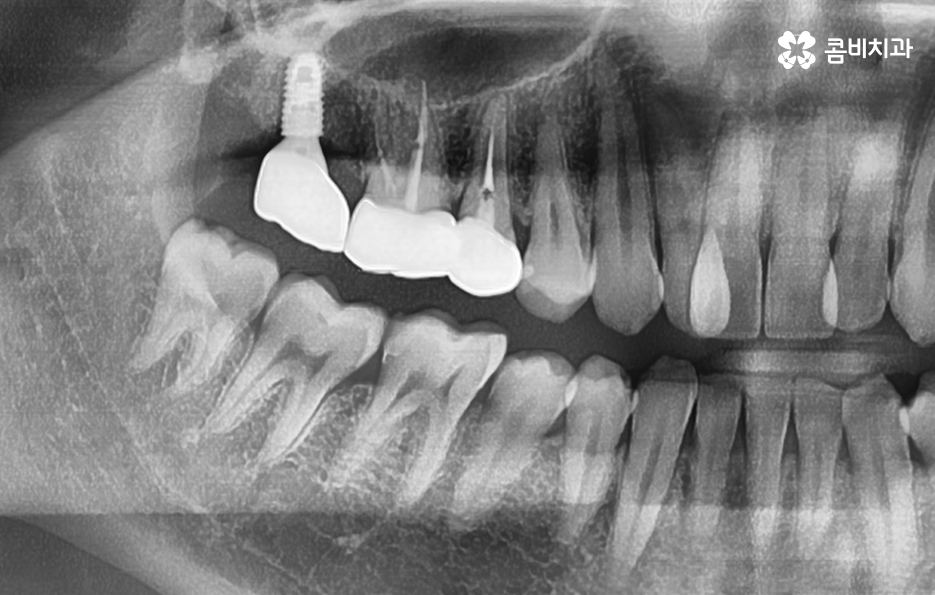

어금니 충치 발치 후에는 바로 임플란트를 해야 하나요

위 사진에서 보여지는 것처럼 어금니는 치아 안쪽에 위치하고 있기 때문에 치아 상실 후에 심미적인 부분에 있어서는 당장 불편함을 못느낄 수 있지만 치아는 저마다 역할과 기능이 있고 저작력에 있어서 밸런스도 무척이나 중요하기 때문에 치아를 잃게 되었다면 별다른 이유가 없다면 즉시 임플란트 치료 계획을 세우시길 권하고 있어요

당장은 반대쪽 어금니로 식사를 해도 괜찮다고 느끼시는 분들도 있지만 장기적으로는 치아 저작력의 밸런스를 잃게 될 수 있고 그로 인해 소화불량이나 턱 관절 장애로도 이어질 수 있는데요. 임플란트를 즉시 권하는 더 중요한 이유로는 치아 발치 후에는 해당 잇몸 뼈가 서서히 흡수되기 때문에 주변 치열이 망가지거나 반대쪽 치아가 내려올 수 있으며 추후에는 임플란트를 하더라도 잇몸 뼈의 부족으로 인해 뼈이식을 추가적으로 해야 할 수 있다는 점에서도 임플란트 치료를 미루지 마시길 권하고 있어요